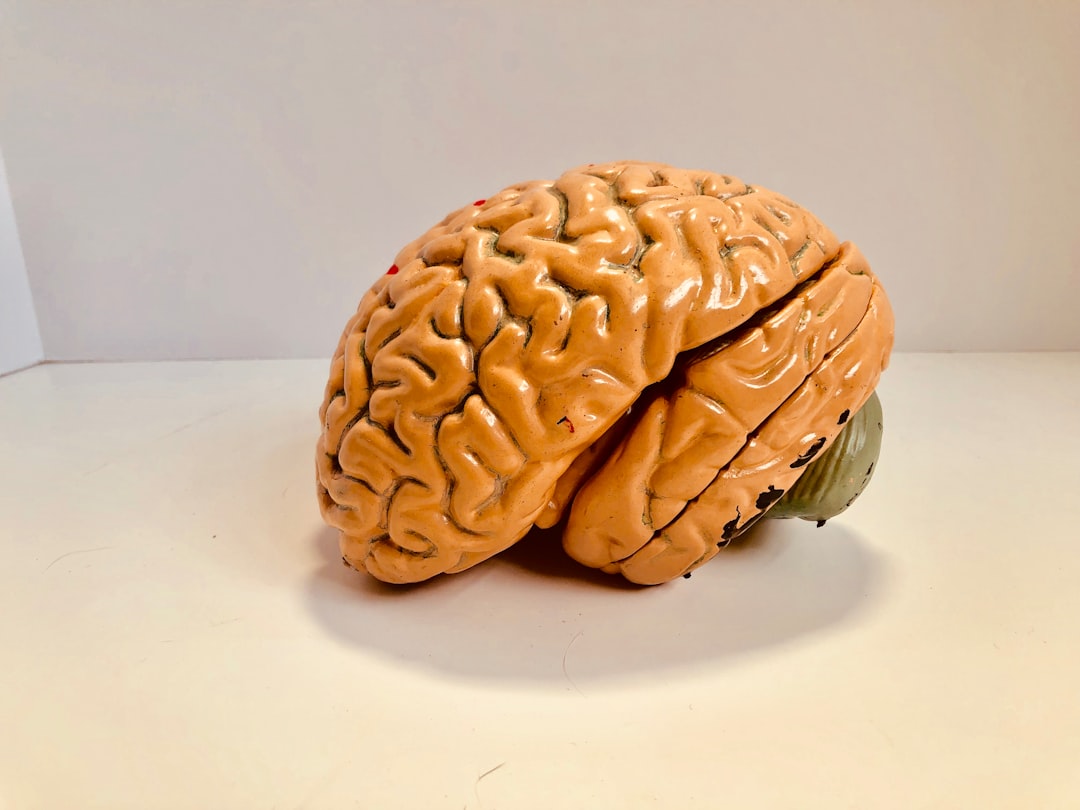

Oytun Erbaş, uyuşturucu bağımlılığını “beynin uyuşturucu tarafından nasıl manipüle edildiğini” anlatarak açıkladı. Uyuşturucu, beynin ödül sistemini manipüle ederek bağımlılığa yol açıyor. Beyin, uyuşturucu ile temas ettiğinde, dopamin adı verilen bir hormon salgılar ve bu hormon, bir tür ödül olarak algılanır. Bu, beynin uyuşturucu kullanımını tekrarlama isteğini artırır.

Akademisyen Erbaş, uyuşturucu bağımlılığının fiziksel ve psikolojik zararları konusunda da bilgi verdi. Fiziksel zararlar arasında, kan basıncının düşmesi, solunum sisteminin çökmesi ve kalp ritminin bozulması yer alıyor. Psikolojik zararlar ise, depresyon, anksiyete ve sosyal izolasyon olarak sıralanıyor.

Oytun Erbaş, uyuşturucu bağımlılığına karşı alınabilecek önlemler konusunda da bilgi verdi. İlk adım, uyuşturucu kullanımını önlemek için bilinçli kararlar almak. İkinci adım, bağımlılığa yol açan durumları tanımlamak ve bu durumları aşmak için destek almak. Üçüncü adım, uyuşturucu kullanımını reddetmek ve sağlıklı yaşam tarzı benimsemek.

Akademisyen Erbaş, uyuşturucu bağımlılığına karşı alınabilecek önlemlerin yanı sıra, bu soruna çözüm bulmak için gerekli adımları atmanın da önemli olduğunu vurguladı. Bu, toplumdaki bilinçli kararlar almaya ve sağlıklı yaşam tarzı benimsemeye bağlı.